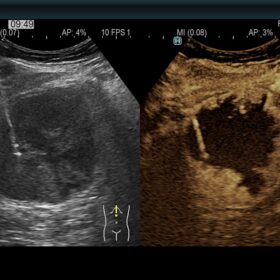

Ultrasound ARIETTA 750 VE – Image Gallery and Videos

Radiology 2D, Color, Contrast and Elasto mode

Radiology

Be prepared for various clinical cases.

- Highly sensitive B-mode and Color Mode

- Advanced Elastography features

- Advanced Fusion Imaging features

- Contrast Imaging